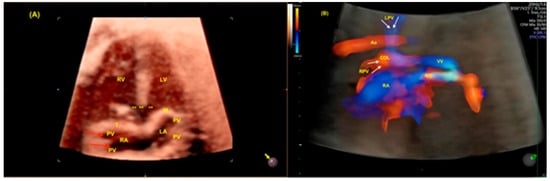

2.1. Anomalous Venous Return

- Malho, A.S.; Bravo-Valenzuela, N.J.; Ximenes, R.; Peixoto, A.B.; Araujo Júnior, E. Antenatal diagnosis of congenital heart disease by 3D ultrasonography using spatiotemporal image correlation with HDlive Flow and HDlive Flow silhouette rendering modes. Ultrasonography 2022, 41, 578–596. [Google Scholar] [CrossRef]

- Tie, H.X.; Ma, B.; Zhang, D.C.; Li, T.G. Prenatal diagnosis of fetal inferior vena cava malformation using HDlive flow combined with spatiotemporal image correlation. Echocardiography 2022, 39, 685–690. [Google Scholar] [CrossRef]

- Li, T.G.; Ma, B.; Gao, Y.H.; Zhang, R.H.; Li, P.L.; Da, Z.Q. Prenatal diagnosis of total anomalous pulmonary venous connection using 2D and HDlive flow combined with spatiotemporal image correlation. Echocardiography 2022, 39, 1269–1275. [Google Scholar] [CrossRef]

- Bravo-Valenzuela, N.J.M.; Peixoto, A.B.; Araujo Júnior, E. Prenatal diagnosis of total anomalous pulmonary venous connection: 2D and 3D echocardiographic findings. J. Clin. Ultrasound 2021, 49, 240–247. [Google Scholar] [CrossRef] [PubMed]